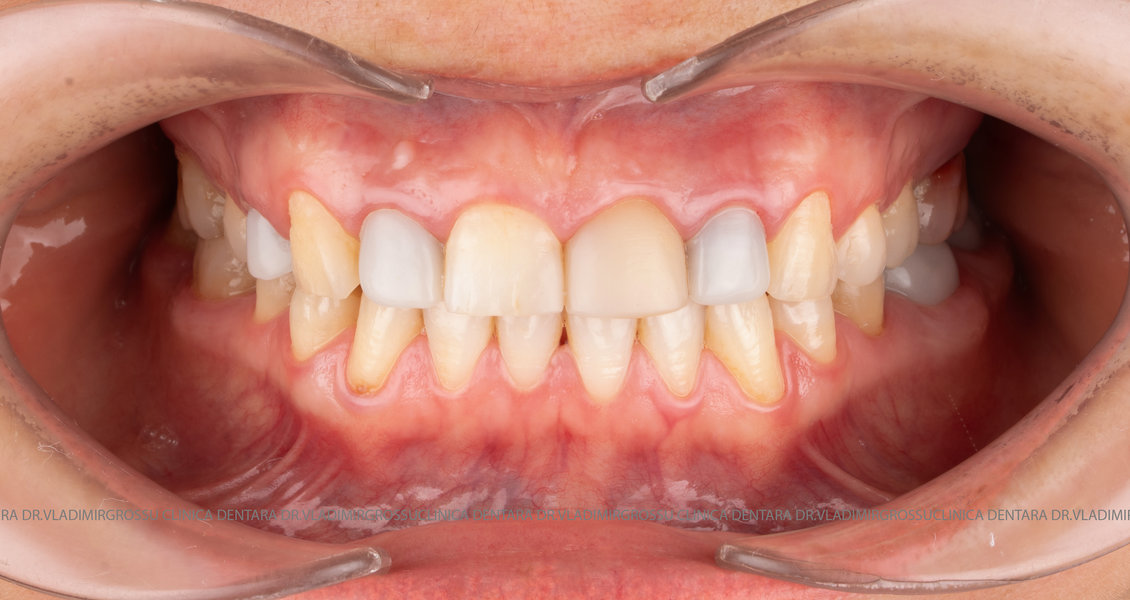

Cazuri clinice

Caz 1

Transformările estetice și impactul reabilitării asupra vieții pacienților

Reabilitarea dentară produce o schimbare vizibilă și profundă în aspectul pacientului, cu efecte pozitive evidente asupra stimei de sine și a calității vieții. Mulți pacienți relatează bucuria redobândirii funcției masticatorii și dispariția complexelor legate de aspectul dentar.